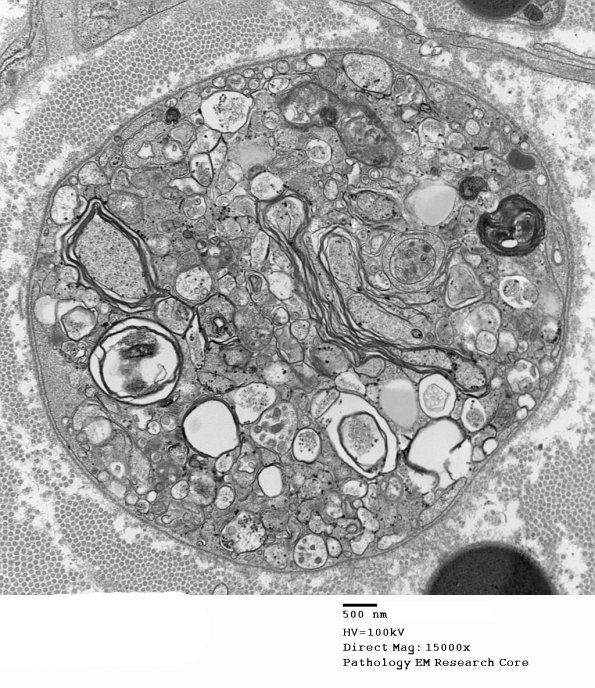

2B1 Axonal Degeneration (Case 7) EM 003 - Copy

2B1,2 Bits of myelin and axoplasm in the parent Schwann cell are found.